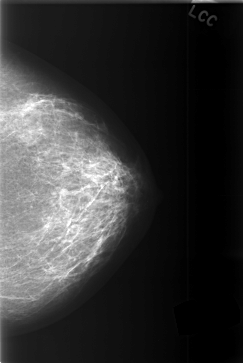

C_0374_1.LEFT_CC

LEFT_CC LINES 5808 PIXELS_PER_LINE 3880 BITS_PER_PIXEL 12 RESOLUTION 50 NON_OVERLAY

LEFT_MLO LINES 5480 PIXELS_PER_LINE 4000 BITS_PER_PIXEL 12 RESOLUTION 50 NON_OVERLAY